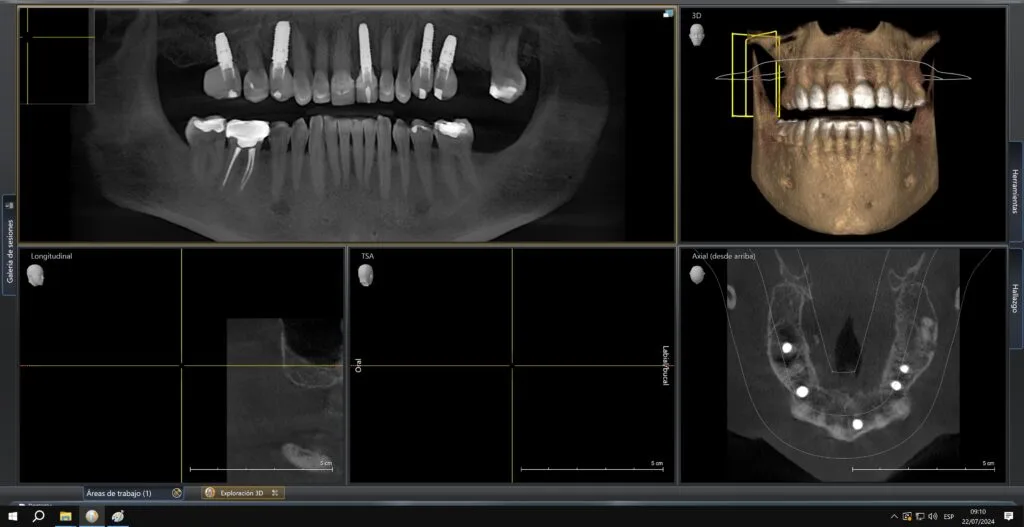

Después de la colocación de los implantes, se espera un período de tres meses para proceder con la fase final del tratamiento.

El tratamiento de implantes dentales se divide en dos etapas principales: la colocación del implante y la instalación de la corona dental.

Después de los tres meses, el tratamiento se completa con la colocación de las coronas protésicas.

Una vez que el implante se ha integrado al hueso, que generalmente tarda 3 meses, se procede a la colocación de la corona dental. Durante esta fase, se toma una impresión para crear una corona que se ajuste perfectamente a tu boca, tanto en forma como en color, garantizando una apariencia completamente natural.

Una corona 3D CAD CAM garantiza un ajuste preciso, excelente estética y colocación en el mismo día, brindando una restauración inmediata y de alta calidad.